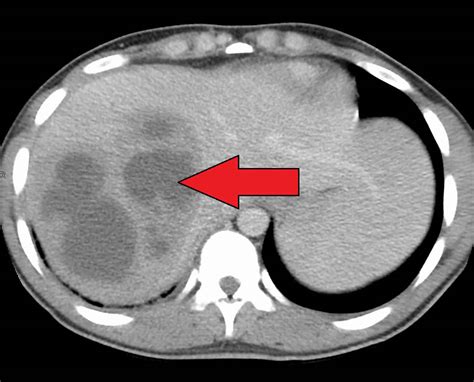

• Imaging Studies: Imaging techniques such as ultrasound, computed tomography (CT) scan, and magnetic resonance imaging (MRI) can visualize the abscess and determine its size and location.

• Percutaneous Drainage: A needle or catheter is inserted through the skin into the abscess to drain the pus. This procedure is often guided by ultrasound or CT scan.